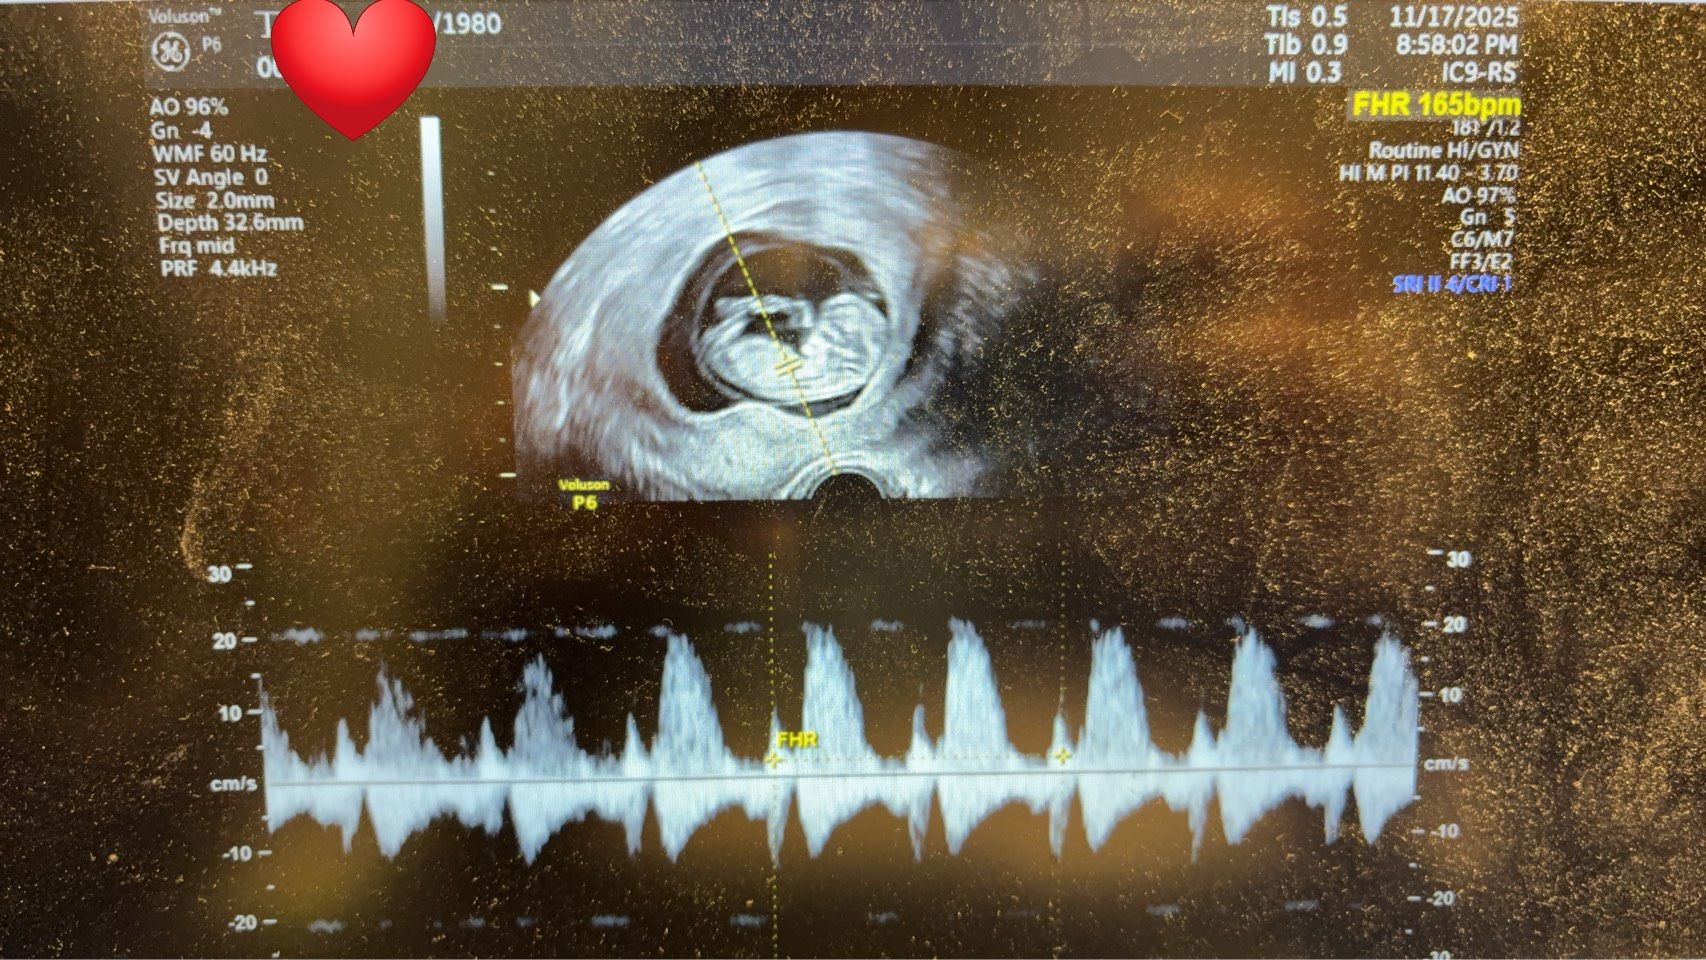

✨ 4顆優質 D3 胚胎,一次植入即成功懷孕! ✨

目前丁小姐已順利懷孕 11週並成功畢業,正式邁向幸福而期待的孕期旅程。